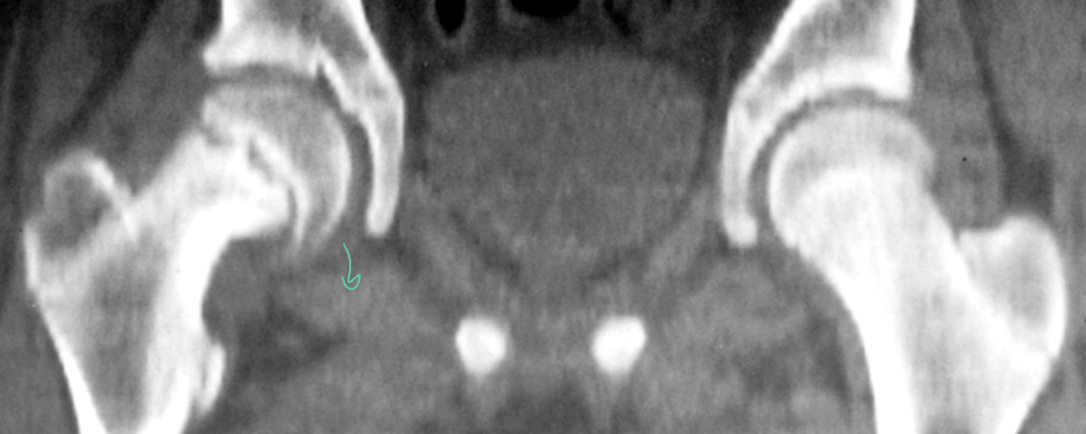

developmental dysplasia of the hip

A

• packaging

• test with Barlow maneuver

• treat with Ortolani maneuver

developmental dysplasia of the hip (DDH)

• packaging and associated conditions: CMT and plagiocephaly, metatarsus adductus, calcaneovalgus

• Barlow and ortolani tests until 3 months old

• use Pavlik harness, hip spicea, osteotomies, ROM and developmentally appropriate activity and strengthening

17

Q

tests for infant hip DDH

• B before O

• barlow test: flex and abducted, then gradually adduct with pressure in posterior direction

• ortolani maneuver: if B test is positive, gentle flexion then abduction, slight anterior traction

can also look at asymmetrical skin folds, atypical gait